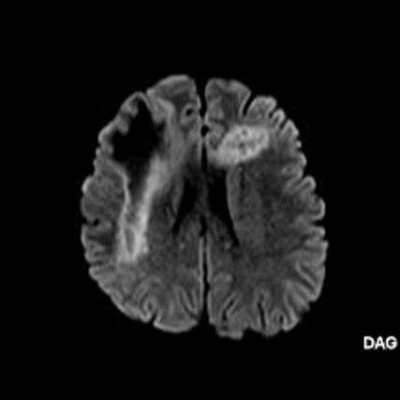

2. B) Aksiyel diffüzyon ağırlıklı serilerde bilateral sağda belirgin frontoparietal subkortikal ve derin periventriküler beyaz cevherde periferal DAG hiperintens ADC hipointens, hafif diffüzyon kısıtlaması (oklar) eşlik etmektedir. IVKM sonrası kesitlerde tarifli alanlarda belirgin kontrast tutulumu (oklar) izlenmedi.